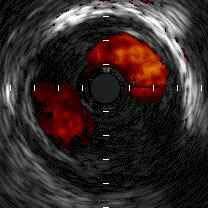

症例のご相談をいたします。症例は60才男性で1990年にUAPにてSVG to RCA SVG to

Lcxの2枝CABGを施行されている方です。Riskは高血圧です。川崎病なし、FHなしです。

術後12年間は胸痛なく、Ca拮抗剤にて血圧も安定しておりました。2002年9月ころよ

り安静時の胸部不快感を自覚されたために10月1日にCAGを施行いたしました。(TBA)

結果、#1 100% #13 100% SVG to RCA patent SVG to Lcx patentでありましたがLAD

に冠動脈瘤を認めました。また#7に75%狭窄を認めます。LAD flowは瘤+狭窄のた

めdelayとなっております。心臓血管外科がいないということもありIVUSをしようと

したら周囲に止められましてIVUSは施行しておりません。